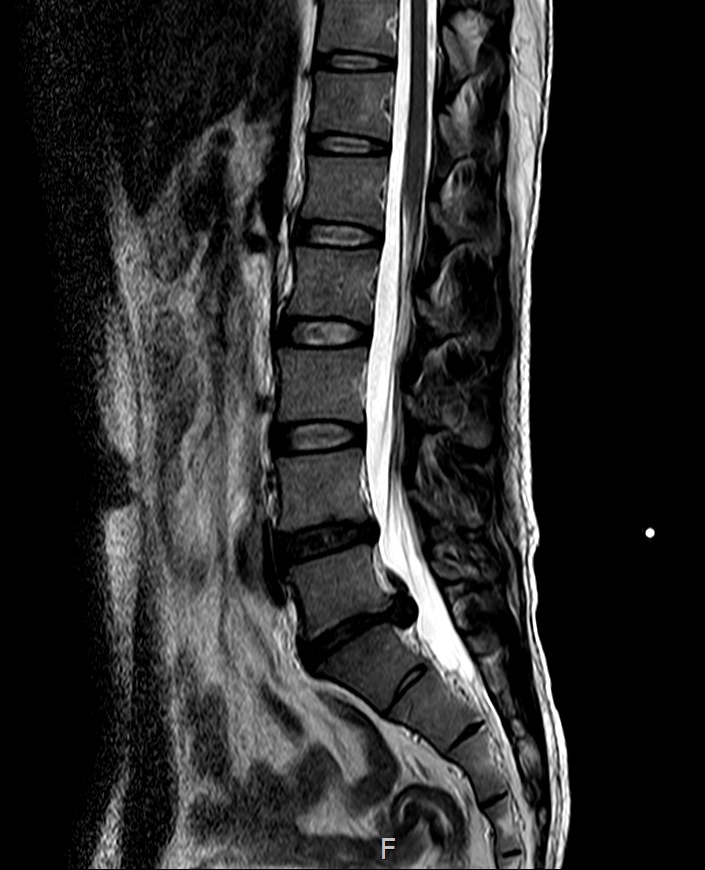

허리상태가 점점 안좋아 짐에 따라 MRI를 찍어보려 병원으로 향했다.

약 15분 정도 대기 후 20분 정도 원통에 들어가 MRI검사를 시작~!

의사 : "지금 상태면 응급수술 들어가야 합니다. 수술 하시겠습니까?"

의사 : "터진정도를 떠나서 흘러내리는데 어떻게 걷죠?.. 까치발 한번 서보세요. 괜찮아요?"

의사 : "판독결과로만 말씀드리면 이경우는 무조건 수술하셔야 합니다"

이미 디스크는 터져서 신경을 완전 짓누르고 있었다... 아 .. 어쩌지..

MRI영상을 보여드리니.. "어우..... 이정도 셨어요.. 이정도면 무조건 수술해야해요.."

의사 : "MRI상태를 봤을 때는 무조건 수술해야하지만, 허리 근력이 어느정도 받쳐주고 버틸만 하시면 굳이 안하셔도 됩니다"